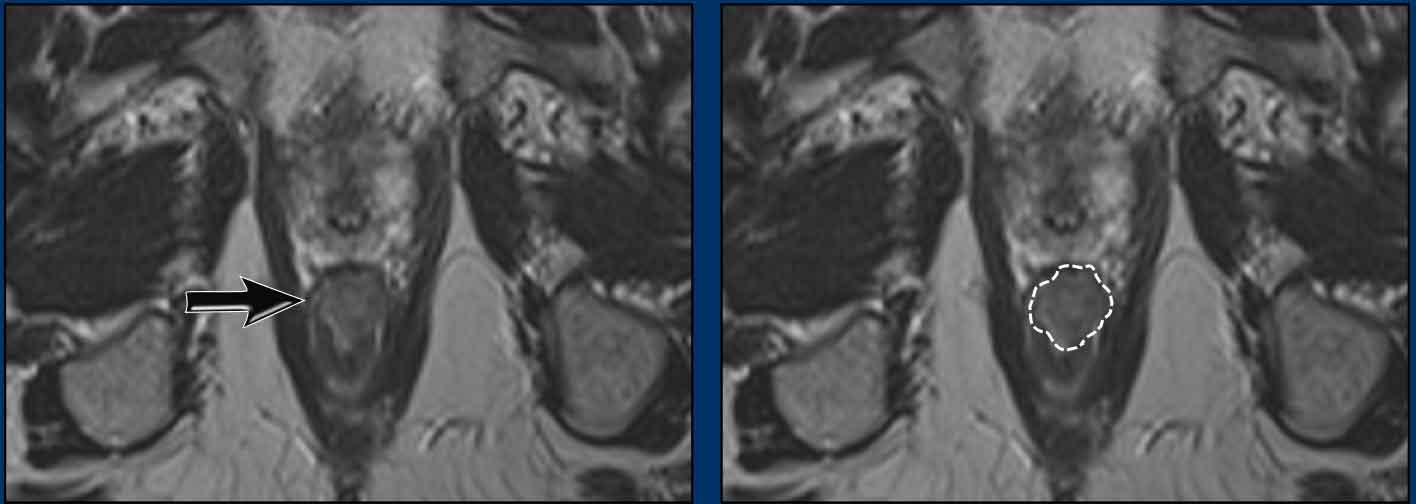

Hình ảnh

Khối u hậu môn ở 1/3 giữa và 1/3 dưới ống hậu môn trước điều trị.

Tiếp tục xem hình ảnh theo dõi…

Đánh giá sau 6 tuần

Đánh giá đáp ứng lần đầu được thực hiện 6 tuần sau phân liều xạ trị cuối cùng.

Có đáp ứng điều trị, tuy nhiên khối u còn sót lại vẫn hiển thị dưới dạng mô tín hiệu trung gian trên MRI chuỗi xung T2W (mũi tên đen) với hạn chế khuếch tán tương ứng (mũi tên trắng).

Tiếp tục xem hình ảnh theo dõi tại thời điểm 6 tháng…

Đánh giá sau 6 tháng

Đánh giá đáp ứng lần hai được thực hiện tại thời điểm 6 tháng sau xạ trị.

Ghi nhận đáp ứng hoàn toàn.